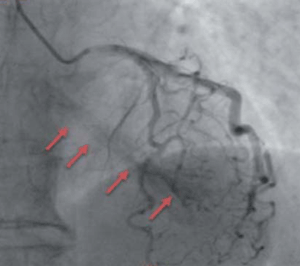

Por estos hallazgos se realiza coronariografía que evidencia múltiples fístulas de la arteria coronaria izquierda a ventrículo izquierdo con fenómeno de robo coronario en territorio de la descendente anterior y coronaria derecha a través de microfístulas, sin arterias epicárdicas identificables, no susceptibles de intervencionismo coronario (figura 1).

Figura 1: Coronariografía en la que se observa robo de flujo de la arteria descendente anterior por múltiples fístulas (flechas rojas), evidenciando la cavidad del ventrículo izquierdo.